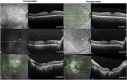

Purpose: Acute vision loss may accompany complete or partial posterior vitreous separation in asteroid hyalosis (AH), and pars plana vitrectomy may resolve these symptoms.

Methods: Six individuals with AH and acute vision loss associated with diagnosed posterior vitreous separation were treated with pars plana vitrectomy, and visual acuity (VA) recovery was monitored for 3 months.

Results: The study patients' preoperative VA ranged from 20/25 to 20/2500 (mean, 20/150; logMAR, 0.88). The average decrease in VA with anterior progression of the hyaloid was logMAR 0.70. Following surgical clearance of the asteroid bodies, VA returned to baseline within 1 month following vitrectomy in 2 eyes, and within 3 months in all eyes. Final VA was 20/20 to 20/200 (mean, 20/35; logMAR, 0.24).

Conclusions: Patients with AH may present with acute onset of severe vision loss in association with posterior vitreous separation. Vitrectomy may be curative and restore vision.